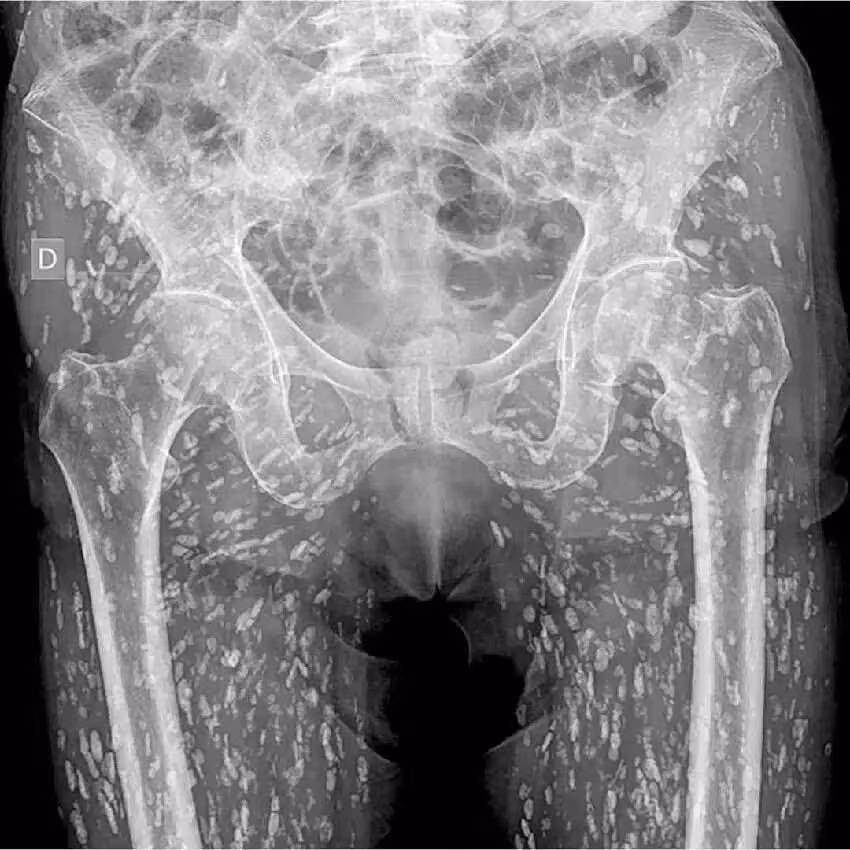

根據媒體《Khaosod》的報導,一名泰國網友「Ai Jaeo Mueang Chan」在臉書分享,自己過去在擔任X光助理時,一名婦人到診所拍攝從髖部到腿部的X光,結果影像一出來布滿詭異陰影,